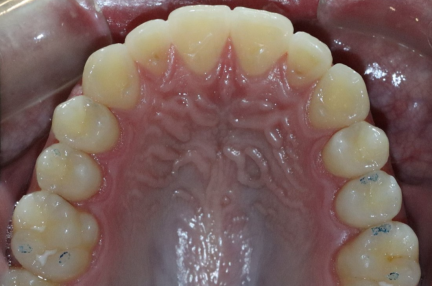

État final

- Arches alignées et coordonnées

- Alignement des deux arcades par dérotation

- Forme de l'arcade améliorée

- La ligne de sourire esthétique a été obtenue

- Des arcades harmoniques ont été obtenues

- L'hyperexpansion de la première prémolaire supérieure droite a été corrigée en planifiant le mouvement lingual avec contrôle simultané du couple.